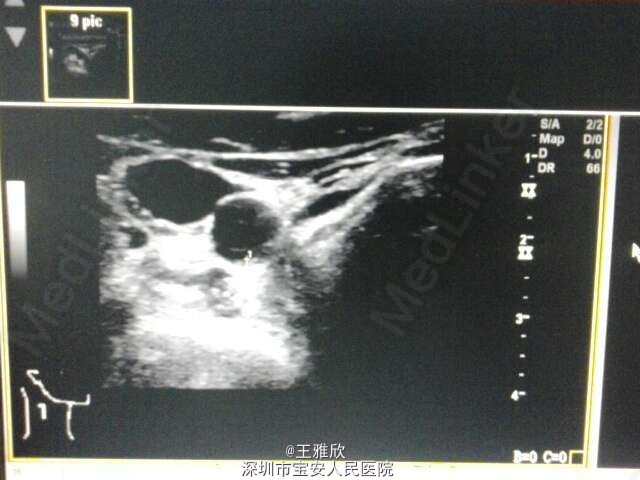

体格检查无特殊,辅助检查:头颅CT:1、轻度脑白质疏松症 2、右侧上颌窦及双侧轻度炎症。头颅MR提示:双侧放射冠、半卵圆中心多发腔隙性脑梗塞,脑动脉硬化。双侧颈动脉+椎动脉:1、双侧颈动脉硬化性改变伴双侧斑块形成,未见明显闭塞,2、双侧椎动脉行走弯曲,左侧椎动脉血流阻力增高,超声心动过图:主动脉硬化、室间隔稍厚,主动脉瓣轻度反流,二尖瓣轻度反流,左室舒张功能降低。